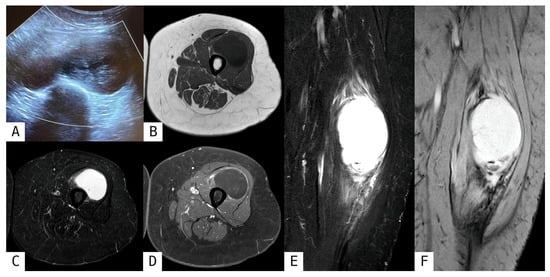

Rare Myxoid Liposarcoma of the Thigh: A Case Report

Introduction: Myxoid liposarcoma (MLPS) is a rare soft tissue sarcoma comprising 5–10% of adult cases, most often in the thigh. Diagnosis is challenging due to nonspecific imaging findings and resemblance to benign lesions. Case Report: A 42-year-old male presented with a [...] Read more.

Introduction: Myxoid liposarcoma (MLPS) is a rare soft tissue sarcoma comprising 5–10% of adult cases, most often in the thigh. Diagnosis is challenging due to nonspecific imaging findings and resemblance to benign lesions. Case Report: A 42-year-old male presented with a painless, enlarging upper right medial thigh mass. CT and ultrasound suggested a complex solid lesion, possibly benign. Outpatient surgical excision revealed a red, gelatinous, non-encapsulated mass. Frozen section suggested a myxomatous spindle cell tumor. Final pathology confirmed MLPS FNCLCC grade 2 (intermediate grade) with DDIT3 rearrangement on fluorescence in situ hybridization (FISH). Margins were negative but close. Postoperative PET scan and Signatera MRD assay were negative for metastasis. Given the tumor’s size (>10 cm) and known radiosensitivity, adjuvant radiotherapy (60–66 Gy) was initiated. Discussion: MLPS features myxoid stroma, plexiform vasculature, and, in high-grade tumors, a round cell component. The FUS::DDIT3 fusion gene is diagnostic. While MRI offers superior soft tissue characterization, definitive diagnosis requires pathology and molecular testing. Surgical excision with negative margins remains standard, with radiotherapy recommended for large tumors or close margins to reduce recurrence. This case highlights the limitations of preoperative imaging and the value of intraoperative pathology in guiding management. Conclusions: Early recognition, accurate diagnosis, and tailored multimodal treatment are essential for MLPS. Given the potential for recurrence, late extrapulmonary metastases, long-term surveillance with imaging, and molecular assays are critical for optimizing outcomes. Full article